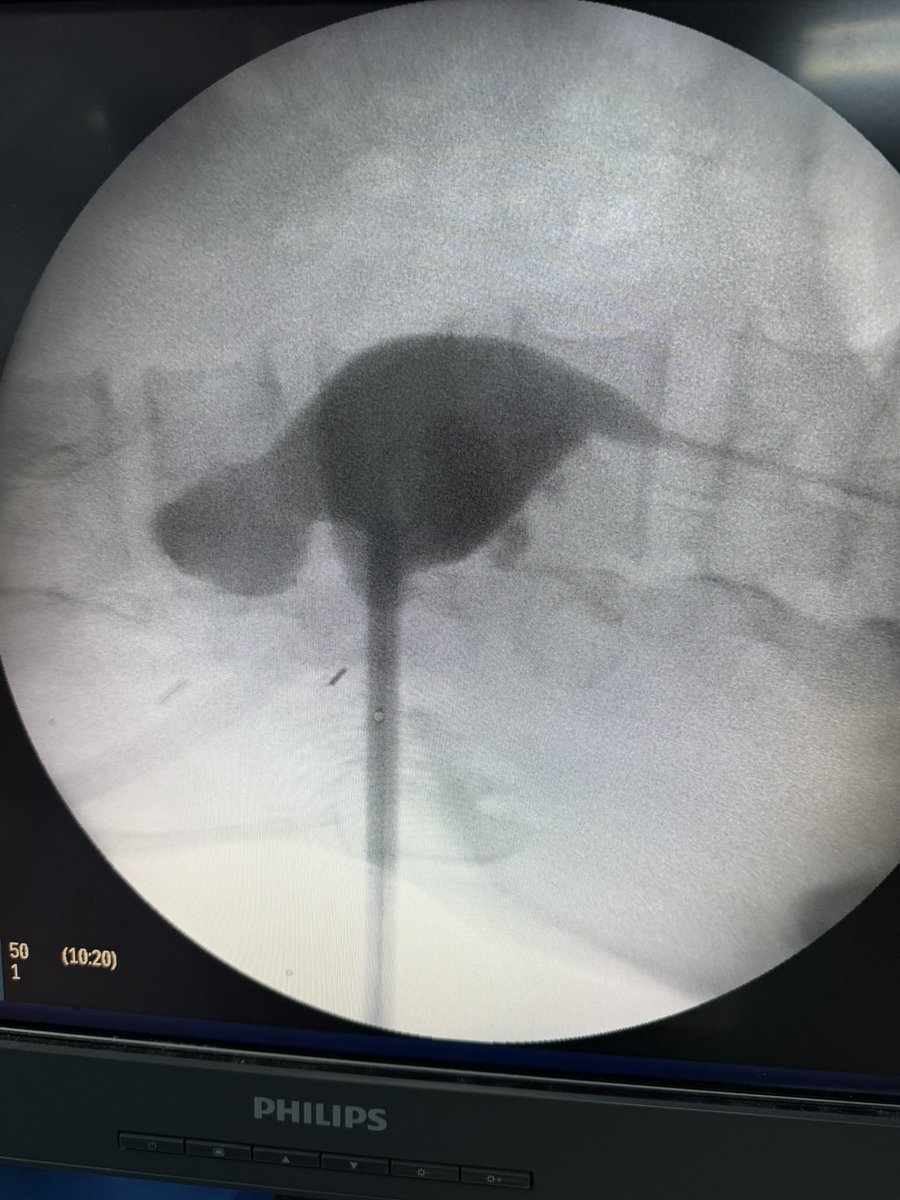

💥 Our Hands-On Course on Ultrasound-Guided PCNL at @CMUN_Urologia was a great success!

An incredible day of practical learning, experience sharing, and passion for advancing minimally invasive surgery